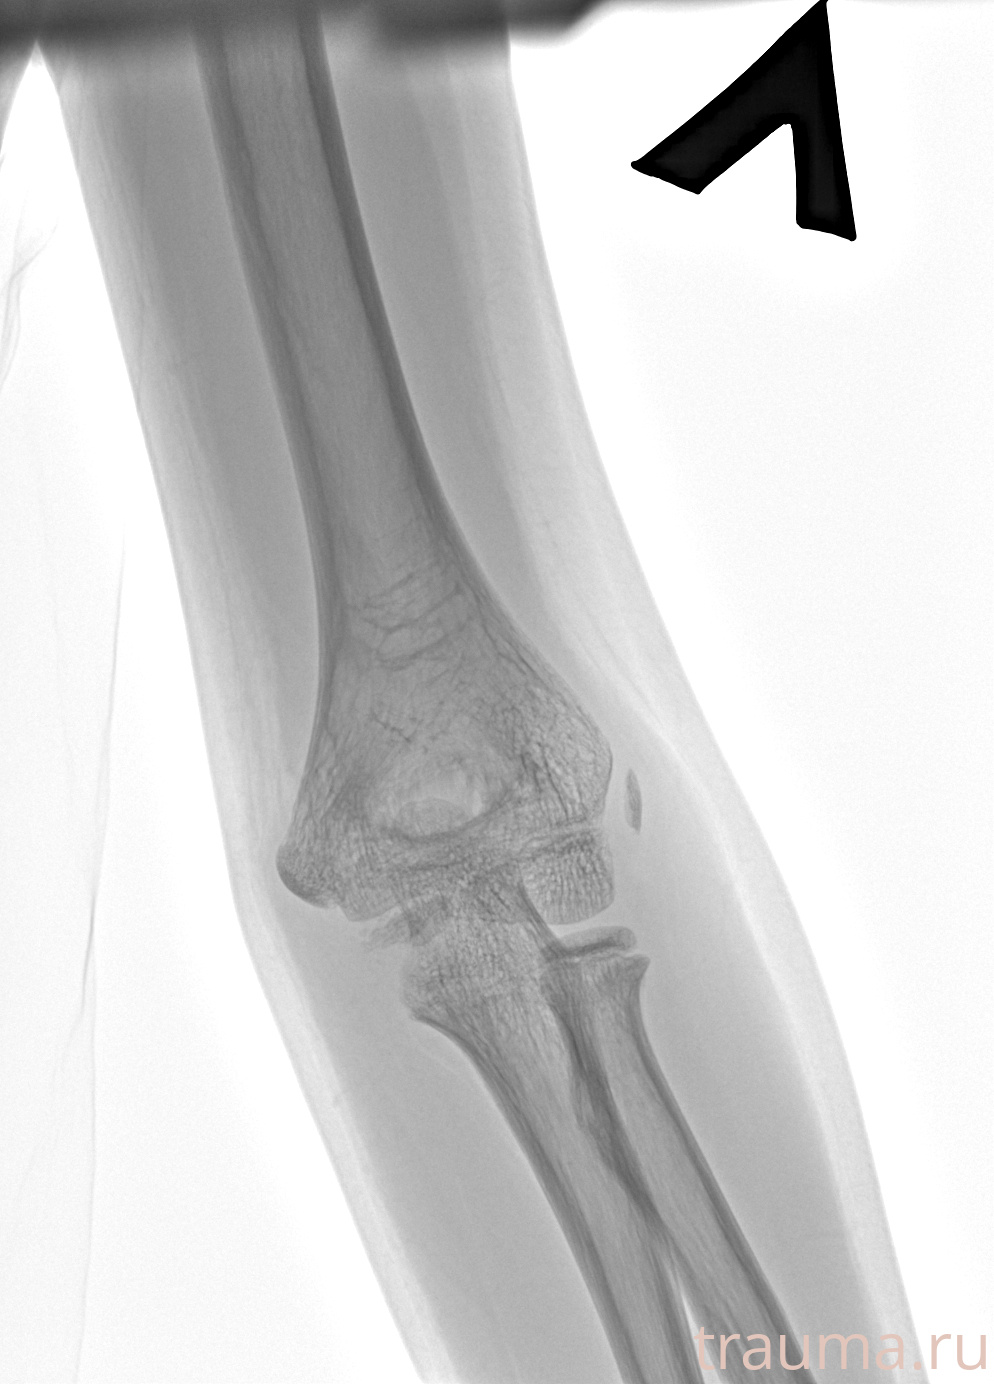

Рентгенограммы

Рентген на дому: по вашему адресу приезжает врач-рентгенолог, травматолог-ортопед с мобильным рентгеновским аппаратом, проводит диагностику травмы или заболевания, делает необходимые рентгенограммы, дает рекомендации по дальнейшему лечению. Получить качественные снимки в домашних условиях возможно благодаря уникальной методике, разработанной МосРентген Центром для института  Склифосовского